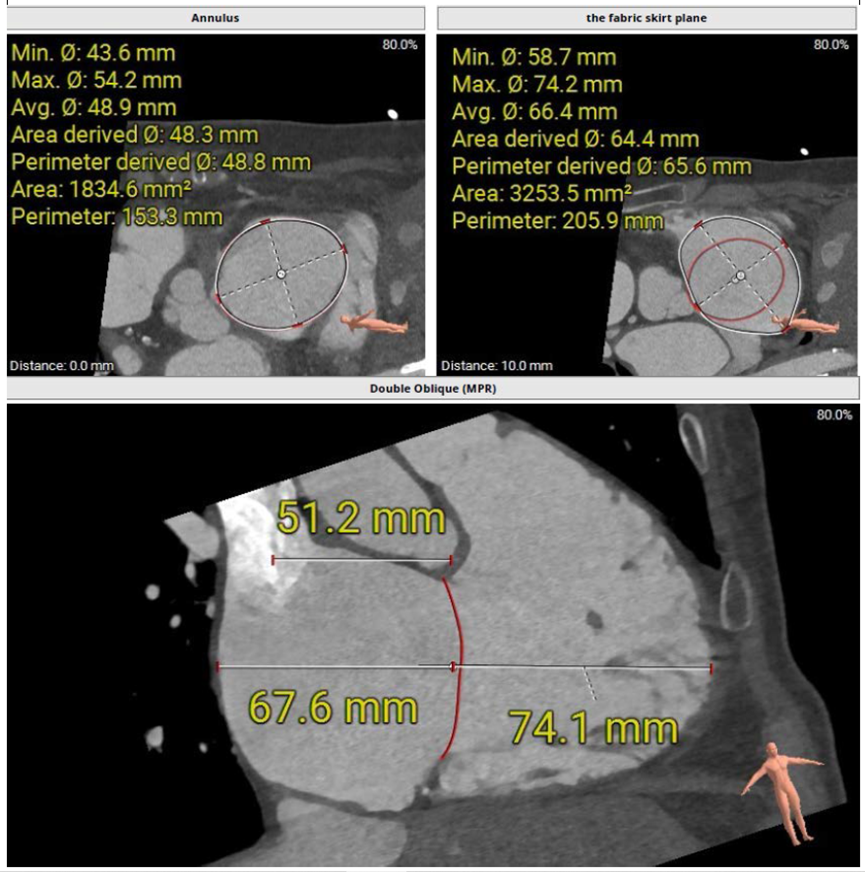

術前CT評估三尖瓣瓣環(huán)大小